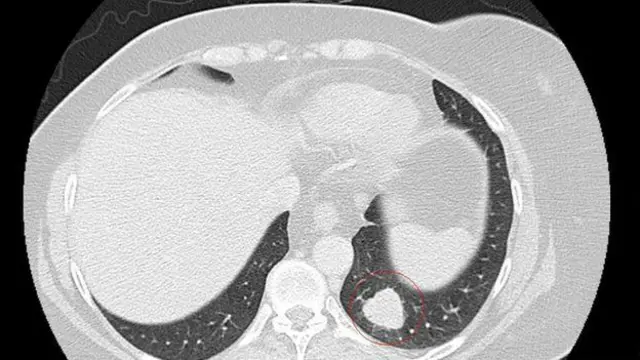

Новоутворення на її обличчі, яке вважалося доброякісним, виявилося насправді меланомою і дало метастази в легені. Лікарі давали їй 18-24 місяці життя.